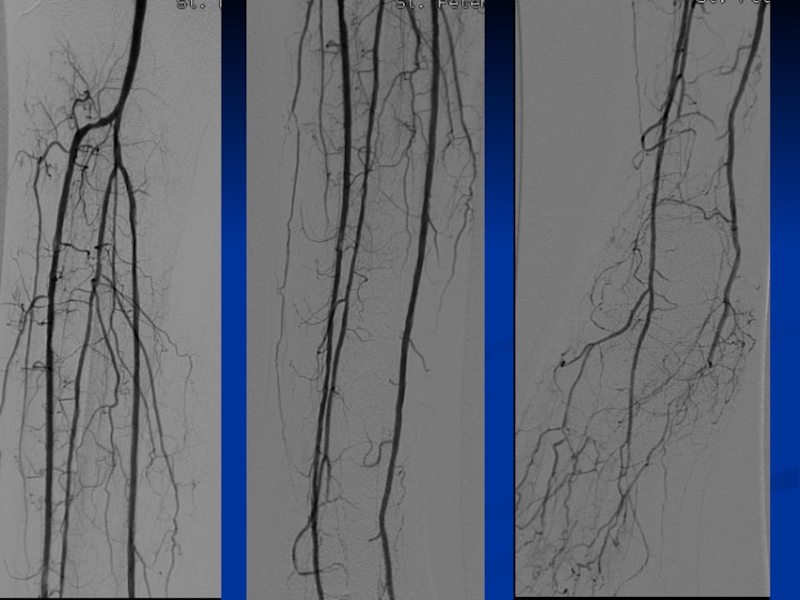

Слайд 21Ретроградный доступ всегда используется в комбинации с антеградным (Safari technique)

Передняя большеберцовая

артерия

Задняя большеберцовая артерия

Малоберцовая артерия – крайне редко

Ретроградный доступ всегда используется в комбинации с антеградным (Safari technique)Передняя большеберцовая артерияЗадняя большеберцовая артерияМалоберцовая артерия – крайне

Слайд 22Safari technique

ПББА

ЗББА

Safari techniqueПББАЗББА